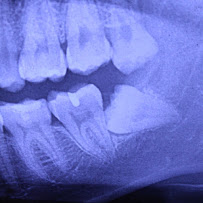

Clínica Dental RV Odontología Integral in Guadalajara is equipped with modern dental technology to support accurate diagnosis and effective treatment across all specialties. Digital X-ray systems reduce patient radiation exposure while producing clear, detailed images for precise clinical decision-making. The clinic's facilities maintain rigorous sterilization and infection control protocols, ensuring patient safety at every visit. Comfortable treatment rooms and a welcoming reception area contribute to a positive patient experience in Guadalajara.